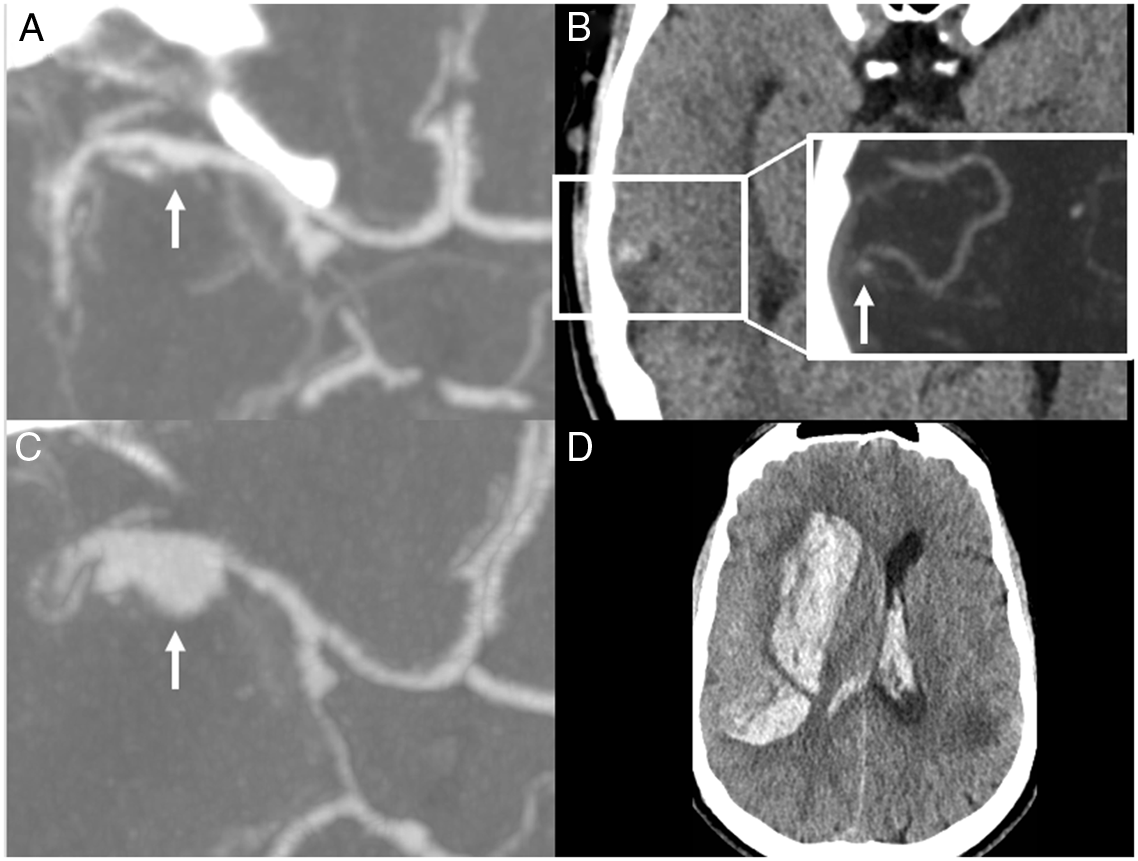

A CTA performed on Day 4 revealed a right MCA mycotic aneurysm at the site of the original occlusion (Figure 2a). Additional right MCA cortical branch aneurysms were also identified, one of which was associated with a new temporal intraparenchymal hematoma (Figure 2b).

Figure 2: Progression of aneurysm in the right middle cerebral artery, leading to rupture and catastrophic bleeding.

On Day 9, another follow-up CTA showed that the right MCA aneurysm had more than doubled in size (Figure 2c). He also developed a new left MCA aneurysm (6 × 5 mm), and the distal right MCA aneurysm had progressed to 2 mm (not shown). On the same day, he developed a thunderclap headache and sudden coma. Urgent CT showed a large right subinsular intraparenchymal hemorrhage with mass effect and intra-ventricular extension (Figure 2d), most likely secondary to rupture of the right MCA aneurysm. After discussion with his family, conservative management was preferred and the patient was listed as a potential organ donor after confirmation of neurological death.